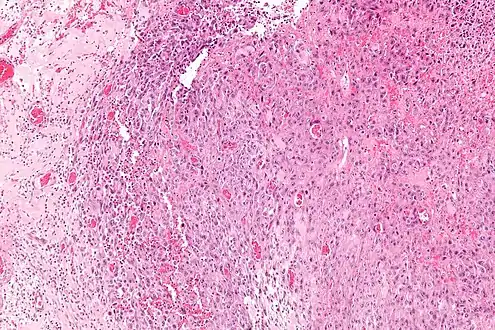

Intermed. mag.